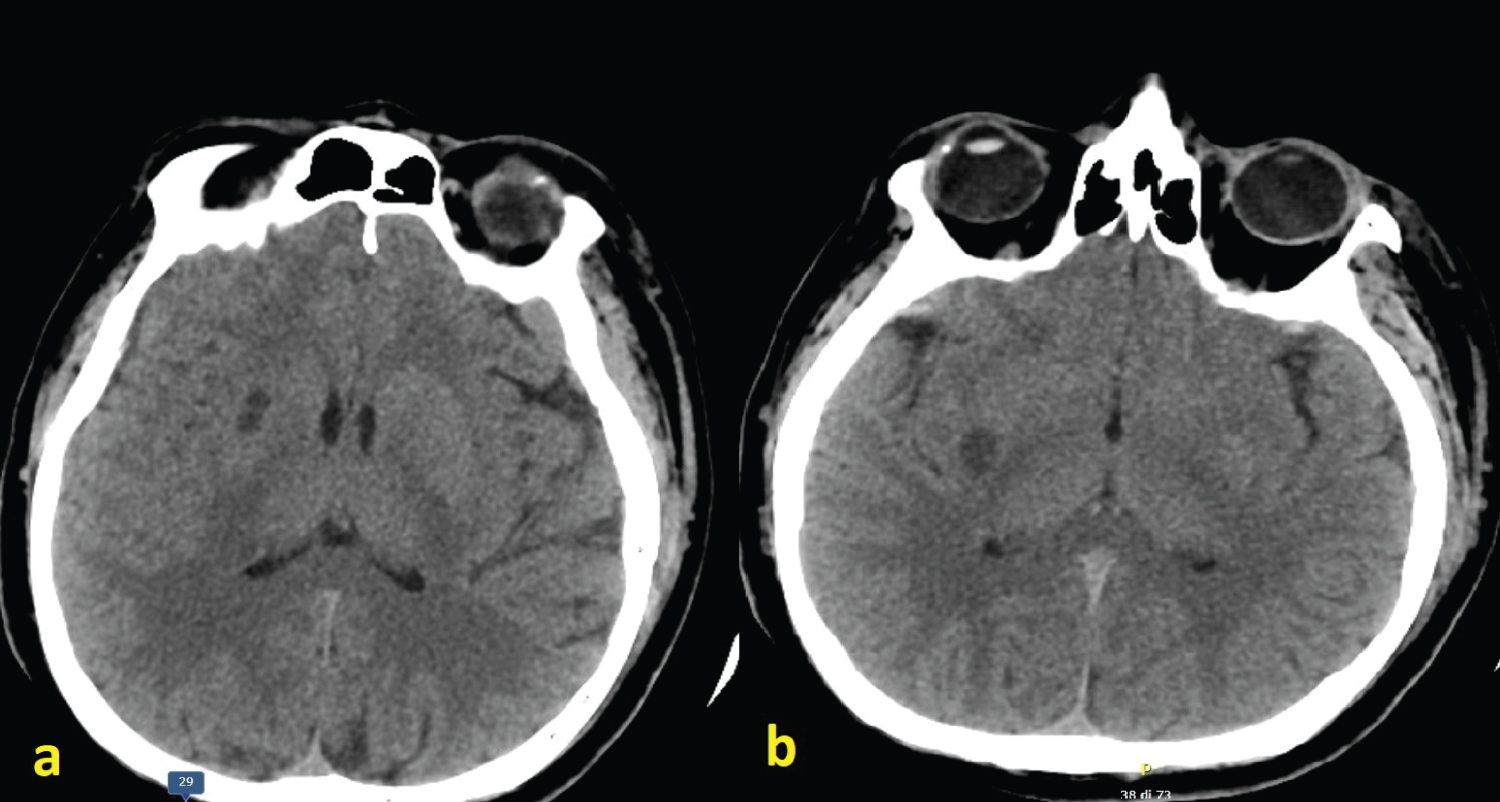

A 43-year-old man was admitted at the ED department as more than 24 hours earlier had complained blurred vision in the right eye and reduced strength in the limbs of his left hemisome (hemiparesis). NIH-Stroke scale (NIHSS) on admission was 4. He was immediately subjected to head CT which showed the presence of a focal hypodense area at the level of the right putamen, compatible with a subacute infarct lesion (Figure 1). The Angio-CT study documented lack of opacification of the right common carotid artery (CCA) approximately 10 mm from his origin and of ispilateral external (ECA) and internal carotid artery (ICA) throughout their all course. A lack of opacification of the M1 and M2 sections of the right Medial Cerebral Artery (MCA) was also evident. The caliber and opacification of the remaining arterial vessels of the Willis' polygon were regular. An atheromatous plaque, partly calcified, determined hemodynamically significant (stenosis > 70-80%) near the origin of the left Internal Carotid Artery (ICA) (Figure 2).

Figure 1: CT brain scan showing hypodense lesions within the right putamen and peri-insular regions due to ischemic infarcts in the territory of lenticulo-striate arteries emerging from the Middle Cerebral Artery (MCA) (a,b). View Figure 1